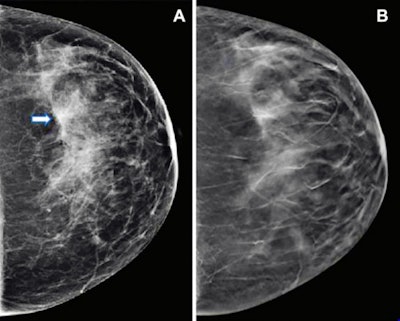

Images show mammography results in a 47-year-old woman who presented for routine screening. (A) Craniocaudal digital mammogram shows scattered fibroglandular densities. On the left digital mammographic craniocaudal view laterally, an asymmetry (arrow) is present. (B) Left craniocaudal DBT imaging shows no suspicious lesion, but rather a superimposition of normal fibroglandular and ligamentous structures. Images and caption courtesy of the RSNA.They evaluated data from 2.5 million screening mammograms from 1.1 million women between the ages of 40 and 79. The women had no prior history of breast cancer and were screened from 2014 to 2020 in five U.S. healthcare systems. The researchers collected information from 1.7 million screening DBT exams and 834,336 screening mammograms from digital mammography.